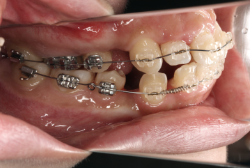

歯科矯正用アンカースクリューを用いた症例(骨格性反対咬合 非抜歯治療)

「ものがうまく噛めない」という主訴で来院したケースです。診断の結果、「骨格性反対咬合に伴う咬合不良+軽度叢生」と判明しました。原因としては特に下顎の左側が過成長したため、骨格性反対咬合になり、特に左側での噛み合わせが非常に悪くなっていると診断しました。初診時の写真を見ると、上下の正中線の大きなズレ、左側の噛み合わせの不良がはっきり分かります(黄色の矢印と緑の矢印は一致しているのが正しい状態です)。

そもそも、このような状態となっているのは骨の大きさに問題があるため生じていますので、場合によっては、「外科矯正」によって下顎の骨を外科的に縮めることで修正します。患者様が外科矯正をご希望されない場合は、従来ですと上下左右の小臼歯抜歯を行い矯正するのが普通です。

今回の患者様の場合は、「外科」も「小臼歯抜歯」も拒否されましたので、歯科矯正用アンカースクリュー(以下 アンカースクリュー)を用いて、下顎の歯列全体を後方に下げるという方法を取りました。

治療中の写真で、アンカースクリューより歯を後ろへ牽引しているのがお分かりいただけるかと思います。牽引を1年ほど続け、途中補助的に上下にゴムをかける(これを顎間ゴムと言います)手法なども追加し、全体で21ヶ月で治療を終えることが出来ました。

結局歯の本数を減らすことなく、すべてご自分の歯を残して、正しい配列と噛み合わせにすることができました。凸凹があまりひどくないため、簡単そうに見えると思いますが、このケースの初診の状態を見ると、熟練の矯正歯科医でも悩みのつきないケースです。まして、外科も出来ない、抜歯もイヤ、と言うことになると、従来の方法では治療不可能と考えられるのですが、アンカースクリューを使うことで最近は不可能が可能となってきました。